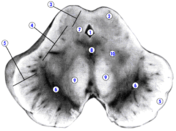

На рисунке: 1 – водопровод мозга (сильвиев водопровод), 2 – верхний холмик четверохолмия, 3 – пластинка четверохолмия, 4 – покрышка среднего мозга, 5 – основание ножки мозга, 6 – черное вещество, 7 – центральное серое вещество, 9 – красное ядро, 10 – медиальная петля.